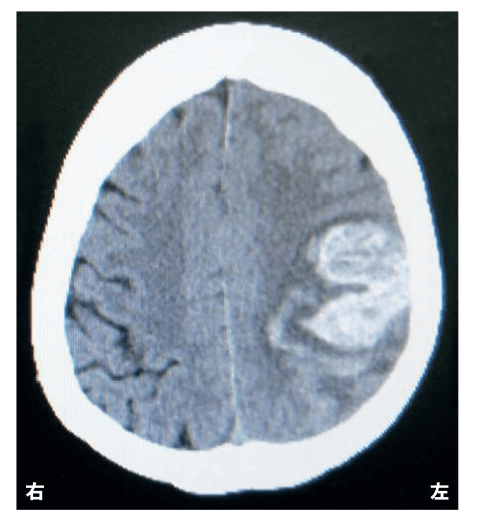

65歳の男性。右利き。突然の意識消失のため救急搬入された。診察時のJCSⅢ-200、血圧210/120 mmHg、脈拍90/分であった。搬送時の頭部CT(下図)を別に示す。

意識を回復した際に認められるのはどれか。2つ選べ。

入院翌日に理学療法が依頼された。JCSⅡ-10、血圧150/100mmHg、脈拍90/分で、バイタルチェックを行いながら、理学療法を開始することになった。

この日に行う訓練で適切なのはどれか。